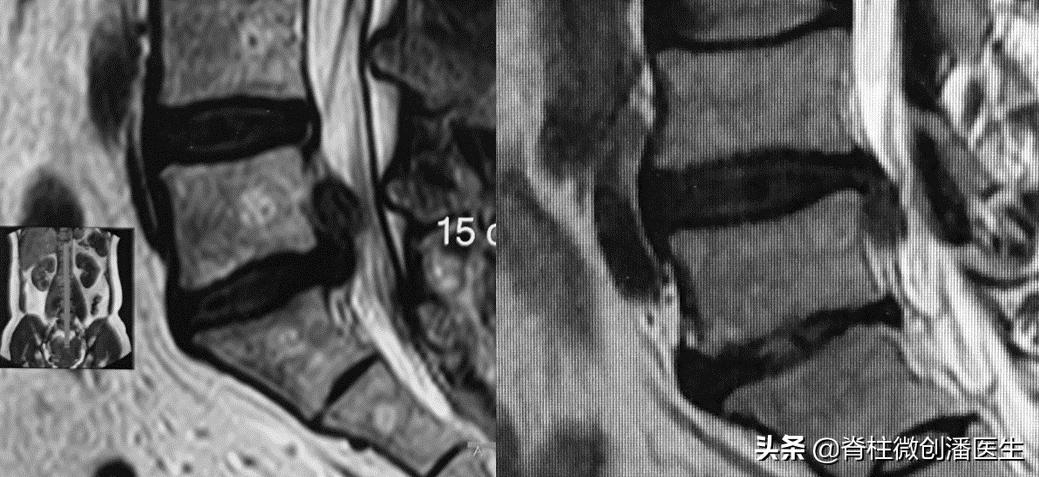

如果在影像学上发现有以下五种征象,往往提示为椎间盘脱出,甚至为游离脱出。

2、椎间盘突出物所占椎管的面积在任一截面上(通常为矢状面)上大于50%。

3、带蒂的椎间盘突出物在矢状位上较长而在冠状位上相对狭窄。

4、突出物位于椎体后方,高于或低于椎间隙,或向外进入椎间孔。